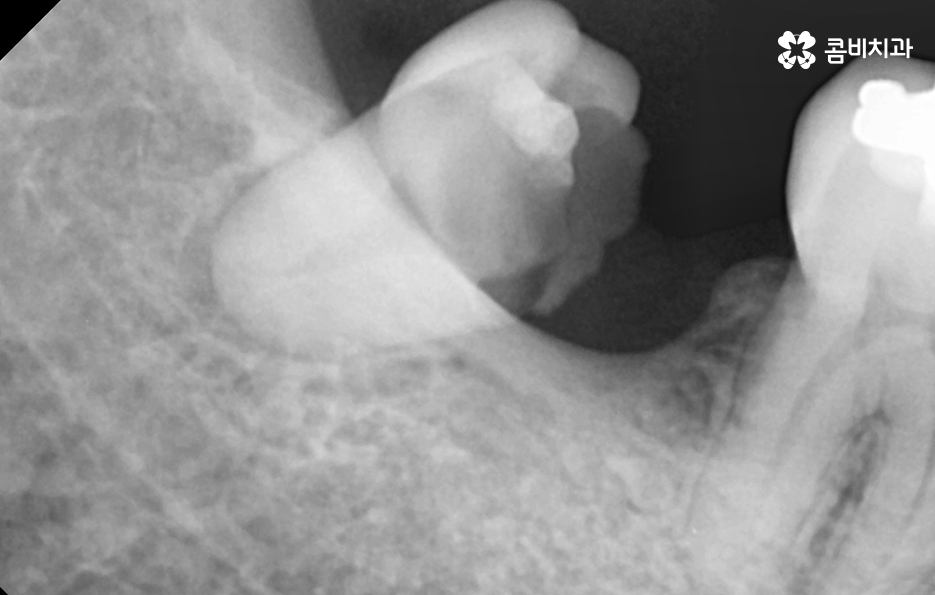

다만 잇몸을 절개하는 정도에 따른 차이와 현재 환자분의 건강 상태도 고려해야 하며 뼈이식이나 잇몸 이식술 같은 치료가 추가적으로 필요한 경우에 좀더 치료 기간이 늘어날 수 있는데요

기본적으로 뼈이식이 필요한 경우에는 치료기간이 짧게는 2개월에서 6개월까지도 늘어날 수 있고 그에 따라 치과의 내원 횟수도 2~3회 정도 더 늘어날 수 있어요.